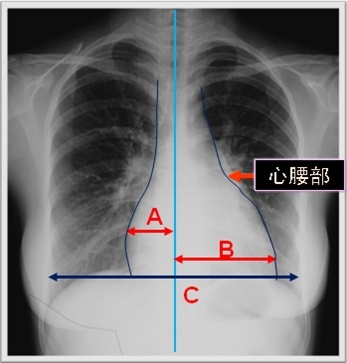

可如何判断心脏的大小呢?

主要根据心胸比例

心胸比例=〔(A+B)/C〕<0.5

轻度增大=0.51~0.55

中度增大=0.56~0.60

重度增大>0.60